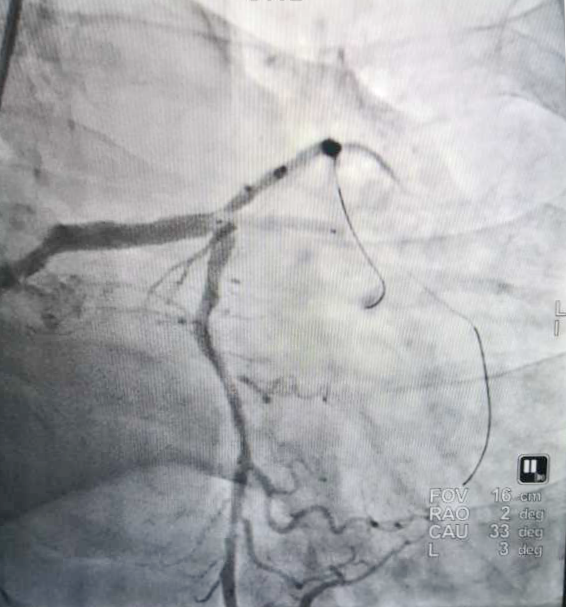

〖微创技术〗开启介入无植入时代——市医院心内科一病区成功开展药物球囊冠状动脉成形术

近日,我院心内科一病区团队成功为一位支架术后再次发生新病变患者实施了经皮冠状动脉药物球囊扩张成形术。该项技术的成功开展,填补了我院心脏病微创技术方面的空白,为广大心脏病患者提供了更加安全、有效的治疗手段。

经皮冠状动脉药物球囊扩张成形术,指经皮穿刺周围动脉将带有药物涂层球囊(DCB)的导管送入冠状动脉到达狭窄节段,扩张球囊,使狭窄管腔扩大,血流畅通,微小的药物载体覆盖在血管壁上,保证药物的持续释放,符合最佳药物代谢。支架内再狭窄是药物球囊首选适应症;其次,血管越细,植入支架后发生血栓和再狭窄风险较高时也适用于DCB;若出现分叉血管,也可通过边支药物球囊扩张,主支植入支架解决;对于部分高血压老年患者,无法耐受长期服药时,和一些外科手术患者需进行短期心脏调整,皆优选DCB。

相较于传统支架及药物涂层支架,DCB能够实现更好的侧支血管的血管开通;减少迟发型支架内血栓形成的风险;保留原有的解剖结构,尤其是一些小血管和血管分叉;广泛用于一些不能或不便于置入支架的病变处,比如一些小血管、支架内再狭窄以及一些分叉病变中侧支血管的治疗;且在一些扭曲的动脉血管中运送更加安全。